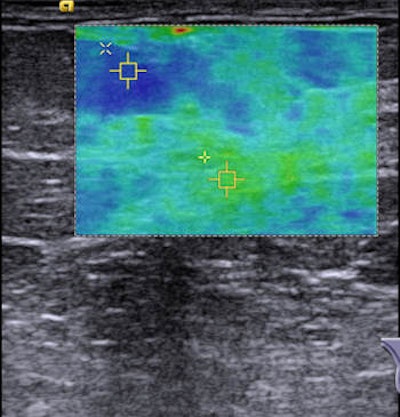

Because the speed of the shear waves propagating through the tissue is proportional to the stiffness of the tissue, a colored map in the region of interest (ROI) gives information on the tissue stiffness in the ROI, according to the authors.

VTIQ image of a healthy breast showing fatty tissue (1.38 m/sec) and parenchyma (3.33 m/sec). Image courtesy of Dr. Michael Golatta.The comparison of mean VTIQ values of parenchyma and fatty tissue in more and less dense breasts (ACR 1 + 2 versus ACR 3 + 4 breasts) yielded no statistically significant difference, the researchers found.

The researchers proposed standard values of VTIQ for healthy breast tissue: Parenchyma showed a mean of 3.23 m/sec (31.3 kPa) with a standard deviation of 0.74 m/sec (1.6 kPa) compared with 2.5 m/sec (18.8 kPa) for fatty tissue with a standard deviation of 0.61 m/sec (1.1 kPa). The difference between the two was statistically significant (p < 0.0001).